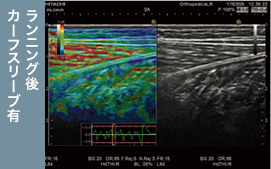

20km走の前後で下腿三頭筋(腓腹筋・ヒラメ筋の内側・外側)の硬度の変化を超音波画像診断装置で測定。カーフスリーブ着用の有無*での比較を行いました。

超音波画像診断装置による検査。

超音波画像診断装置による検査。

ランニング後の筋硬度変化率

ランニング翌朝の体調、全身疲労、ふくらはぎ痛のすべてについて、カーフスリーブを装着したグループの全員が「状態が良い」と回答しました。筋硬化度を測定する検査では、カーフスリーブを装着したほうが腓腹筋やヒラメ筋の硬化度が低く抑えられ、特にふくらはぎ外側の筋硬化を抑える効果が高いことが判明。